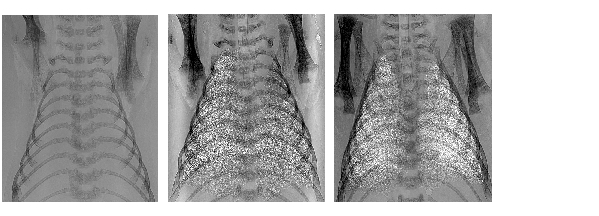

rob1.jpg